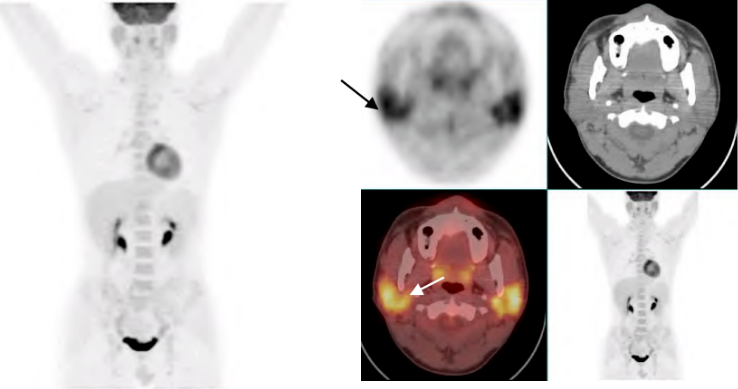

干燥综合征:可见双侧唾液腺代谢增高。